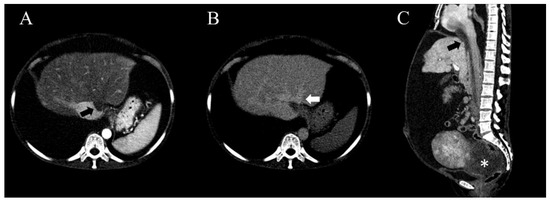

2. Case Presentation